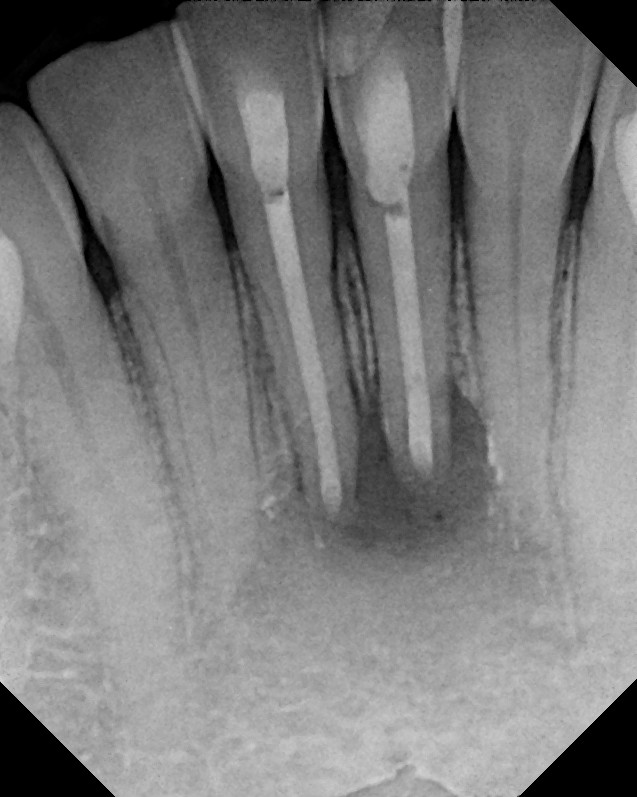

From www.clairemontendodontist.com

Before & After Photos Endodontic Surgery (Apicoectomies) Gallery Apicoectomy And Endodontic eliminate persistent endodontic pathogens: apicoectomy, often deemed a last resort in endodontic treatments, is a fascinating procedure. While not as commonly discussed as root canals or tooth extractions, it holds a special place in dental care. an apicoectomy is a common dental procedure where inflamed gum tissue and the end of the root of your tooth is.. Apicoectomy And Endodontic.